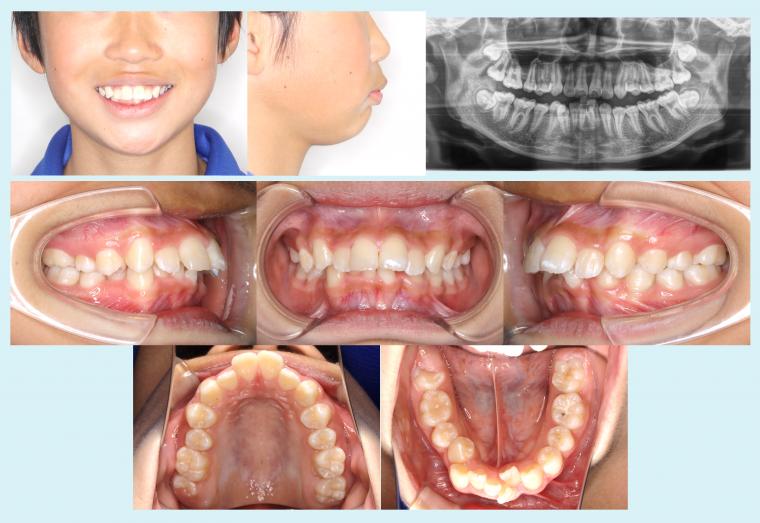

2026.04.29 #52 13歳4か月から上顎前突の治療を行った症例 「かかりつけ歯科より紹介を受け、歯並びが悪いので矯正について相談したい」とのことで来院された患者様です。治療前は、上の前歯が著しく唇側に傾斜していて、下の歯列はデコボコしていました。横顔を見ると口元が... 症例集(表側矯正)